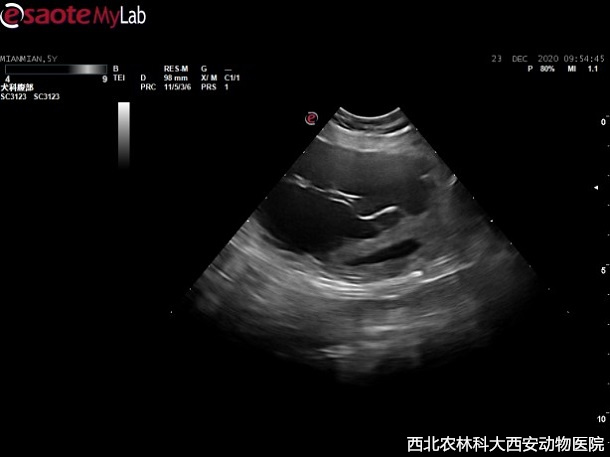

輔助檢查:主人自帶腹部平片顯示前列腺增大,膀胱前列腺區(qū)域有一明顯占位待查。超聲提示:前列腺增生且伴有囊腫,緊鄰前列腺和膀胱可見無回聲異常囊性占位,與周圍組織有聯(lián)系,疑似粘連見(圖1)。

圖一